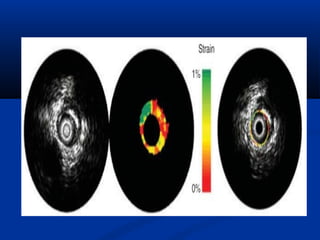

Novel Invasive Imaging Modalities

OPTICAL COHERENCE TOMOGRAPHY

INTEGRATED BACKSCATTER ANALYSIS

(“VIRTUAL HISTOLOGY”).

   INTRACORONARY THERMOGRAPHY.

   PALPOGRAPHY.

   COMPUTATIONAL FLOW DYNAMICS.